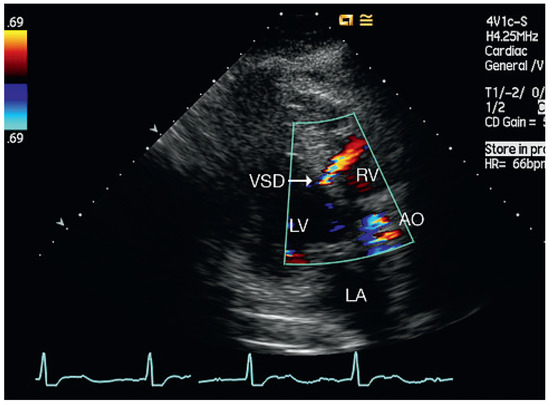

Muscular Ventricular Septal Defect After Mitral and Aortic Valve Replacement

by Augusto Aragão, Dorothea Vogel and Christoph Schmidt

Cardiovasc. Med. 2010, 13(5), 167; https://doi.org/10.4414/cvm.2010.01500 - 26 May 2010

We describe a case series of five patients who were referred to our cardiac rehabilitation department after mitral or aortic valve replacement, and whose transthoracic echocardiographic studies showed postoperative muscular septal defects. Full article